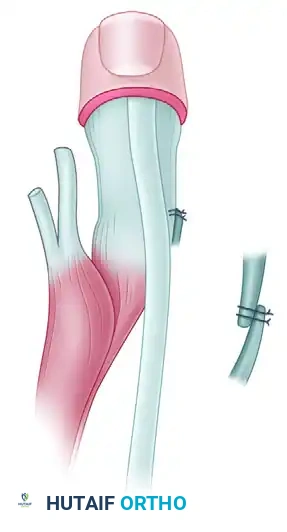

* Upton and Taghinia Technique: Advocates for avoiding complicated dorsal and volar flaps entirely due to the high risk of tip necrosis. Instead, they utilize a simple incision separating the glabrous from the dorsal skin surfaces.

Upton and Taghinia technique: Incisions within the cleft are placed precisely at the juncture of the glabrous and dorsal skin. A small trap-door flap is utilized for commissure lining between the ring and transposed index finger, ensuring robust vascularity.